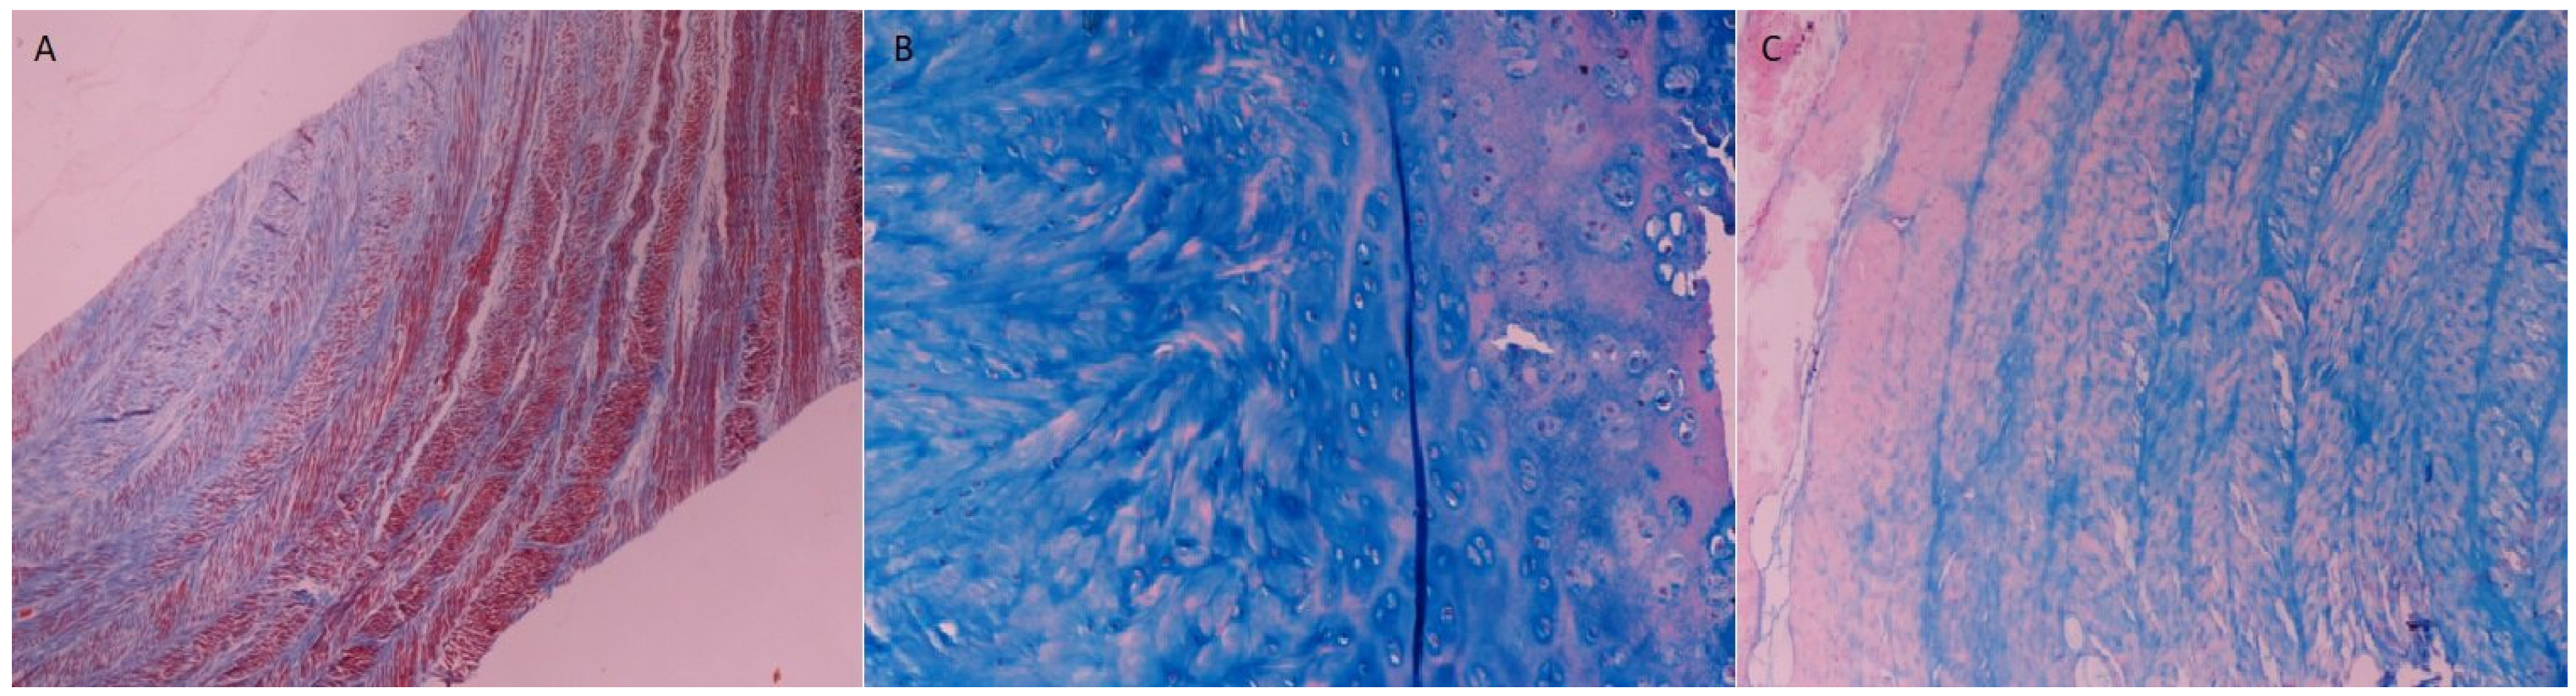

2.3. Histological Assessment

4.3. Histological Evaluation

- Koch, C.; Kandziora, F.; Huenigen, H.; Plendl, J. Histological evaluation of the sheep’s cervical spine segment 3/4--a histomorphological and histomorphometrical study. Anat. Histol. Embryol. 2008, 37, 200–204. [Google Scholar] [CrossRef]